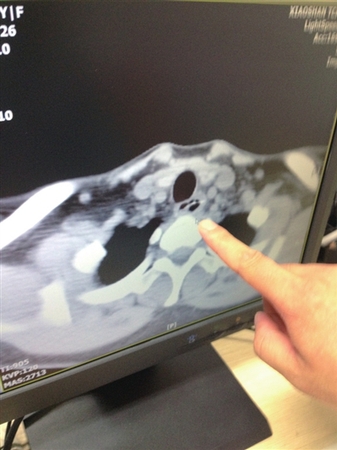

两年来,家住青白江的28岁女子杨女士肛周反复发炎、流脓,可算是吃了不少苦头。一开始,杨女士以为是普通的肛瘘病症,只是通过简单的消炎药处理,但始终未见好转。前不久,不堪忍受病痛折磨的她,终于鼓起勇气到青白江区人民医院做了手术。令她想不到的是,让其“坐立不安”的“罪魁”,竟是一根6厘米长的粗鱼刺,卡在距肛门约10厘米处的狭小直肠腔隙中!

两年前,杨女士发现自己肛周出现反复发炎、流脓现象,但因患病部位隐私,不便就医,羞涩的杨女士只是在药店或诊所买了一些消炎药使用。杨女士告诉医生,用药后情况倒是有所好转,可是却始终治标不治本,炎症继续复发,久治不愈,让她苦不堪言。

后来,杨女士鼓起勇气来到医院就医?!耙缴?,我肛周反复发炎、流脓,持续了快两年?!备菅钆康母髦种⒆疵枋觯缴豢嫉恼锒弦哺胀ǖ母仞≈⑾嗤?,开药后进行治疗。但是,杨女士在用药后炎症仍然比较反复。